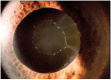

Genetic and genomic studies, including genome-wide association studies (GWAS) have accelerated the discovery of genes contributing to glaucoma, the leading cause of irreversible blindness world-wide. Glaucoma can occur at all ages, with Mendelian inheritance typical for the rare early onset disease (before age 40) and complex inheritance evident in common adult-onset forms of disease. Recent studies have suggested possible therapeutic targets for some patients with early-onset glaucoma based on the molecular and cellular events caused by MYOC, OPTN and TBK1 mutations. Diagnostic genetic tests using early-onset glaucoma genes are also proving useful for pre-symptomatic disease detection and genetic counseling. Recent GWAS completed for three types of common adult-onset glaucoma have identified novel loci for POAG (primary-open-angle glaucoma) (ABCA1, AFAP1, GMDS, PMM2, TGFBR3, FNDC3B, ARHGEF12, GAS7, FOXC1, ATXN2, TXNRD2); PACG (primary angle-closure glaucoma (EPDR1, CHAT, GLIS3, FERMT2, DPM2-FAM102); and exfoliation syndrome (XFS) glaucoma (CACNA1A). In total sixteen genomic regions have been associated with POAG (including the normal tension glaucoma (NTG) subgroup), 8 with PACG and 2 with XFS. These studies are defining important biological pathways and processes that contribute to disease pathogenesis.